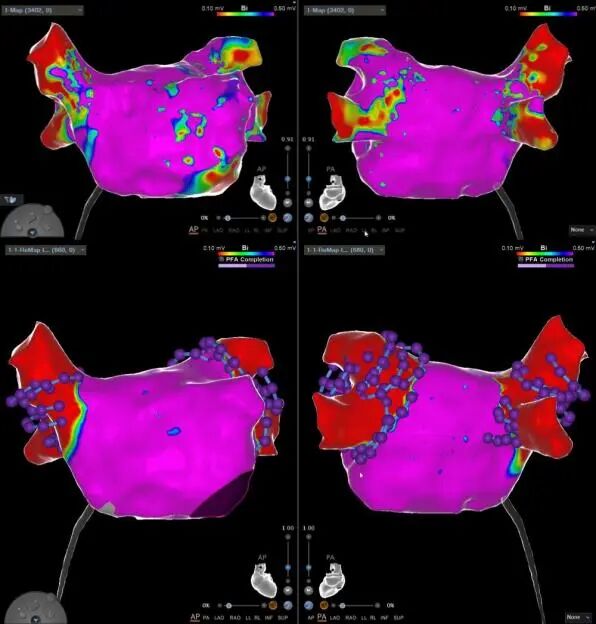

三维解剖重建,手术路径实时追踪

VARIPULSE可与CARTO系统无缝集成,全程三维可视,能够还原左房解剖,追踪消融损伤路径,帮助术者以更安心、高效的方式开展手术。它不仅能与心腔内超声(ICE)产品进行整合,提供实时成像,保障低/零射线手术的顺利开展,还可通过局部阻抗TPI显示电极与组织的贴靠程度,来确保有效放电。